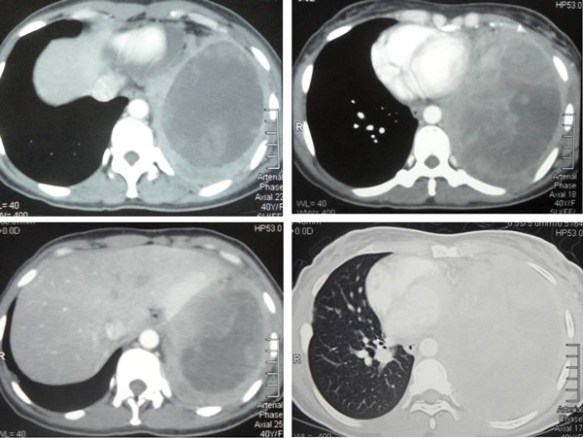

I had a chance to talk to his doctor who told me my brother had anaplastic thyroid cancer. In addition, there were extensive metastases in his lungs and liver. Without doubt – by just looking at the CT scan images (below) – I knew that his days were numbered. No treatment would be able to save him.

On top of this aggressive, rare cancer he also had metastases in his lung and liver. His metastasis was very serious indeed. There is no way anyone can pretend to be a “hero” trying to save him. Added to that was the metastasis to the liver. I was not able to know how extensive it was because I was not able to see the CT scan of his liver.